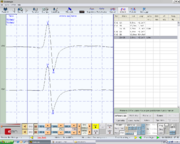

| 13:32, 18 August 2023 | Immagine5.bmp.png (file) |  |

95 KB | Gianni | 1 | |